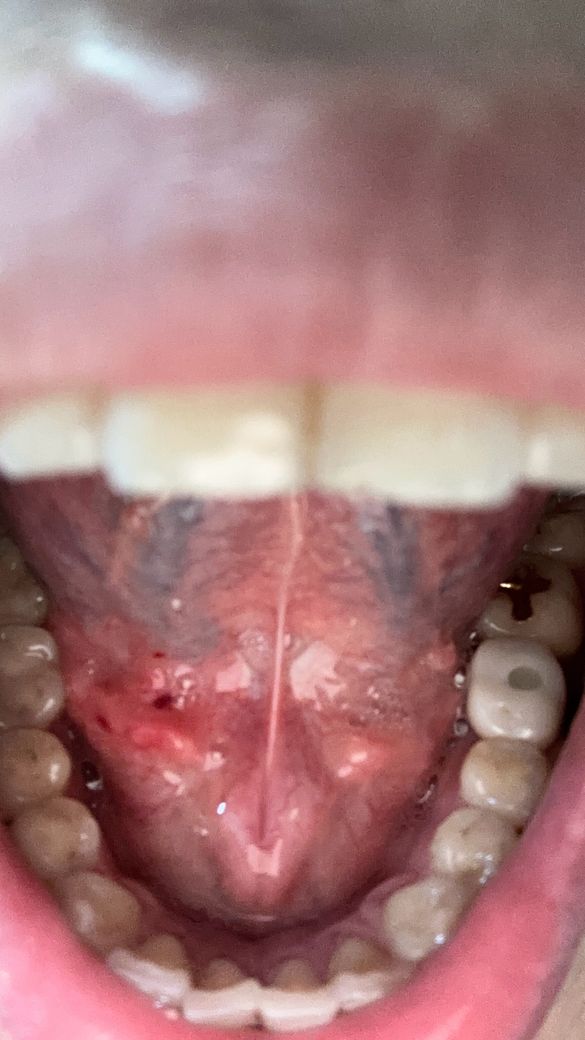

양치하다가 칫솔로 눌렀는데 아파지고 빨개진거같아요

빨갛게 된부분이 있는것같고 그래서 이거 병원가봐야되는지 그냥 냅둬도 괜찮음지 궁금해요 어떻게하는게 좋을까요?? 병원은 무슨과인가요?

• 3번 째 사진